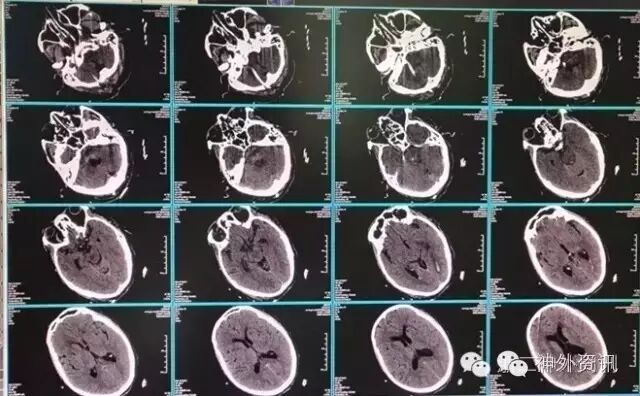

辅助检查: CT:小脑、脑干后部血肿,破入第四脑室及两侧侧脑室后角。按多田氏公式计算血肿量(体积=π/6×长×宽×层面数×层厚)约为20ml(图1)。

图1. 入院CT检查示桥脑出血,血肿约20ml。